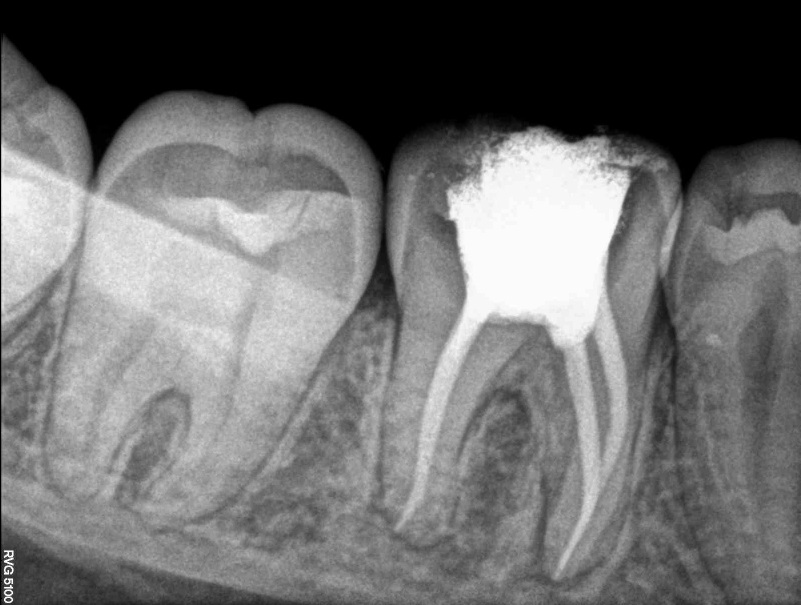

When the inside of the tooth is diseased or injured, the pulp tissue dies. If this tissue is not removed, the tooth gets infected and may cause pain. We provide root canal treatment to save the natural tooth. The dentist removes the diseased pulp, cleans the root canal (the inside chamber of the tooth), and seals it to protect it. Most of the time a root canal procedure can be done with little or no discomfort in one to two visits. Dentists recommend an artificial crown after root canal treatment because it will help stop future infections and strengthen/stabilize the tooth. In most case, the tooth should last a lifetime if you regularly care for your teeth and gums.

State-of-the-Art FacilitiesAt Dental Lounge, we use state-of-the-art facilities and advanced technology to provide you with the best possible care. From digital X-rays to rotary endodontics, we have the tools and technology to make your root canal treatment as efficient and comfortable as possible.